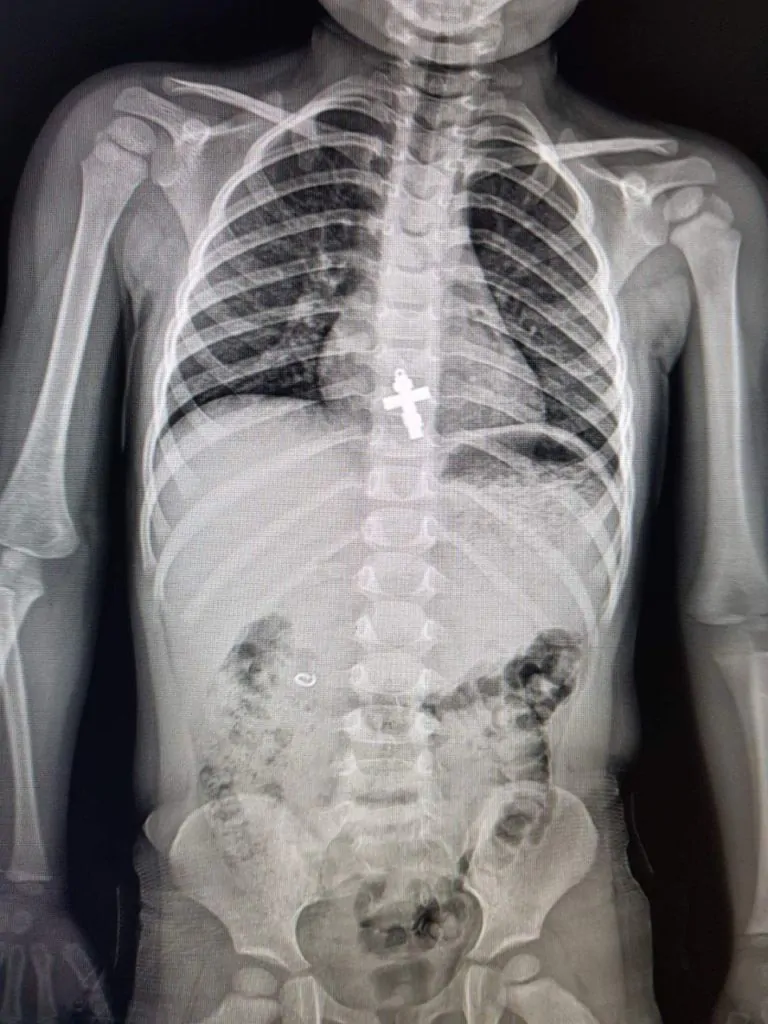

Лікар-ендоскопіст та дитячий хірург Олександр Сльозко розповів, що впродовж квітня медики ендоскопічно діставали з бронхів підлітків цвях та канцелярську кнопку, а зі стравоходу дворічної дитини — натільний хрестик.